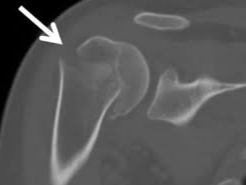

어깨에 골절이 발생하면 일상 전체가 마비되는 기분을 느끼는 것도 무리는 아닙니다. 특히 쇄골, 상완골 근위부, 견갑골 부위에 골절이 생기면 수술이 필요하며, 수술 이후의 재활과 물리치료는 단순히 통증을 없애는 것을 넘어, 관절 가동 범위의 회복과 장기적인 기능 정상화를 위한 핵심 단계입니다. 또한 어깨 골절 수술 이후 본격적으로 시작되는 재활 치료와 도수치료의 현실적인 문제는 ‘비용’과 ‘보험 적용 여부’입니다.